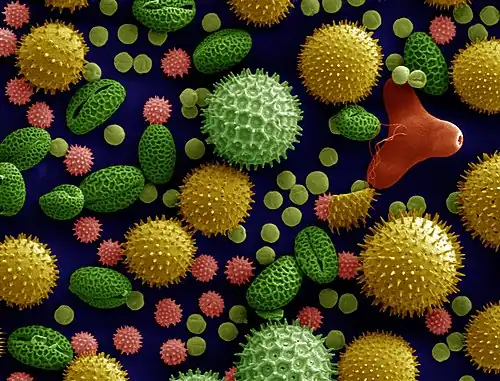

L'allergène peut être le pollen (dans le cadre du rhume des foins) mais aussi les acariens, ainsi que d'autres produits.

Les allergènes peuvent être des poils d'animaux, des acariens, des poussières ou des pollens (on parle alors de pollinose, de rhinite allergique saisonnière, de rhume des foins).

- En 2017 une étude sur les effets de deux polluants oxydants (O3 et NO2) sur du pollen en suspension (de platane ; Platanus x acerifolia s'est basée sur 3 techniques : immunoempreinte, spectroscopie photoélectronique infrarouge et rayons X[12]. La première a clairement mis en évidence un effet d'augmentation d'allergénicité du pollen[12]. Les deux autres ont montré que la composition élémentaire de surface de ce pollen avait (en 6 heures) changé sous l'effet de ces polluants communs. En outre, certains de ces changements dépendaient des polluants, et ils apparaissent à des niveaux de pollution inférieurs aux seuils réglementaires[12]. In vitro, six heures d'exposition à 0,061 ppm d'O3 : 0,025 ppm de NO2 et 0,060 et 0,031 ppm du mélange O3 + NO2 suffisent à induire des changements d'allergénicité du pollen, plus ou moins selon le polluant testé (gaz ou mélange de gaz)[12]. Ce travail a aussi montré qu'un même gaz oxydant (O3 ou NO2) peut interagir différemment selon l'allergène considéré[12]. Selon les auteurs, « lors de son voyage dans l'air, la paroi pollinique subit des modifications de ses composants induites par la pollution atmosphérique, ce qui peut compromettre la fonction pollinique »[12].

La rhinite allergique saisonnière est appelée également pollinose, « rhinoconjonctivite allergique aux pollens », ou plus communément « rhume des foins ». Elle s'oppose aux rhinites dites « pérennes » qui sont, elles, provoquées par une substance allergisante non saisonnière (les acariens, par exemple).

Ses principales manifestations sont éternuements, rhinorrhée, obstruction nasale, démangeaisons nasales et oculaires, larmoiement. Ces symptômes surviennent à la suite d'une exposition à des pollens allergisants, dont la présence dans l'air est variable selon les saisons. En Europe occidentale, par exemple, il s'agit d'espèces comme le noisetier et l'aulne à la fin de l'hiver, suivis du bouleau, puis du chêne au printemps, des graminées en début d'été, de l'ambroisie et du plantain en fin d'été[20]. Les conditions météorologiques influent également : la concentration en pollens dans l'air est plus élevée par temps chaud et sec.